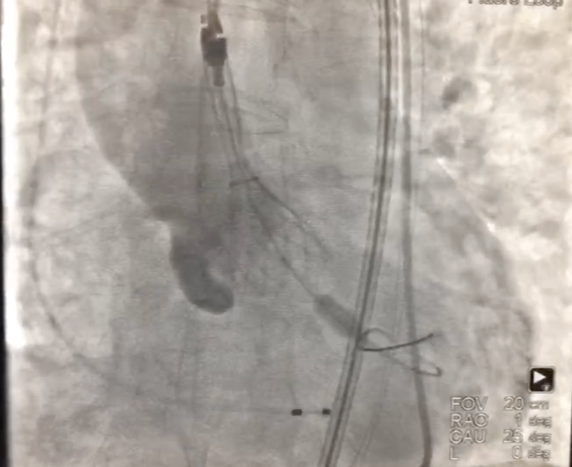

1、经右股动脉将Emboshield Nav6放栓塞装置输送至左、右颈内动脉。

2、经左股动脉入路,顺利跨瓣后,选取20 mm球囊于180 bpm下快速起搏预扩,显示无漏,左、右冠脉未受影响,但可见左冠窦、无冠窦巨大钙化团块。